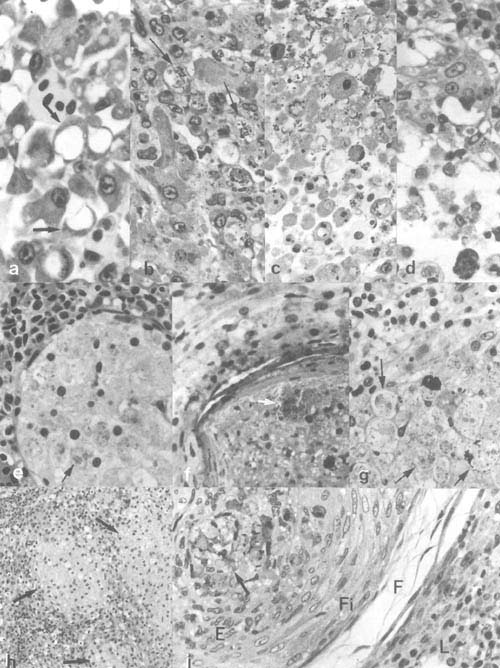

Plate 3. Bacterial infections: a,b. Dropsy in carp from Kajansi farm, Uganda (× 0.8). c. Exophthalmus and cornea hyperplasia in eyes of Oreochromis sp. from Kajansi farm, Uganda (× 2.5). d. Ulcerating skin lesions in Synodontis afrofisheri from north Lake Victoria (× 0.8). e. Vibrio parahemoliticus (arrow) in kidney blood of farmed tilapia hybrid in Israel. f. V. parahemoliticus (arrow) in macrophage aggregate in spleen of a fish of the same group as e. g. Inflammatory lesions in winter stored tilapia hybrid with Pseudomonas sp. as presumptive causative agent. h–g. Histopathological process in tilapia hybrid spleen (h,j) and liver (i) due to pasteurellosis, from granulomatous lesion to liquifactious necrosis.

Plate 4. Bacterial infections continued: a-g. Pasteurellosis in cichlid fishes: a. Hepatocyte degeneration in tilapia-hybrid liver. b. degeneration and death of cells invaded by the bacteria; c,d. the resulting disintegration of the tissue due to infection (same fish). e–g. Pasteurellosis in angel fish (Pterophyllum scalare), showing nodular, bacteria loaded (arrows) lesions (abcesses) with gradually disintegrating macrophage-like cells. h,i. Epitheloid granulomatous lesions with acid fast positive bacteria (Mycobacteria) (arrows) in estuarine grey mullets from Israel (E, epitheloid cells; F, loose outer and, Fi, dense inner layers of fibroblasts; L, surrounding spleen tissue).

Plate 3. Bacterial infections (legend p. 25)

Plate 4. Bacterial infections continued (legend p. 25)